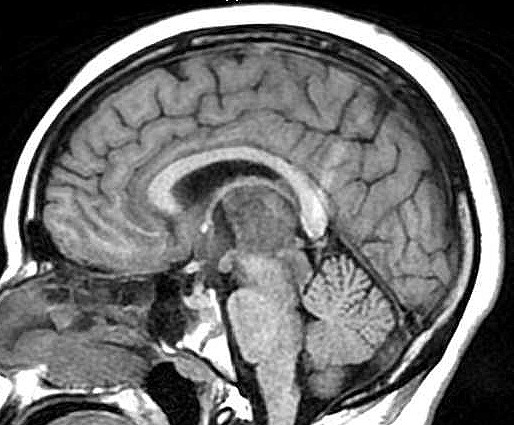

| Fem. 17a. |

| Nódulo sólido homogêneo preenchendo o III ventrículo, com limites precisos, com hipossinal em T1 e hipersinal em T2 e FLAIR, que se impregna por contraste paramagnético. Lesão menor implantada no assoalho do IV ventrículo provavelmente representa disseminação por via liquórica. |

| SAGITAIS, T1 SEM CONTRASTE | T1 COM CONTRASTE | |